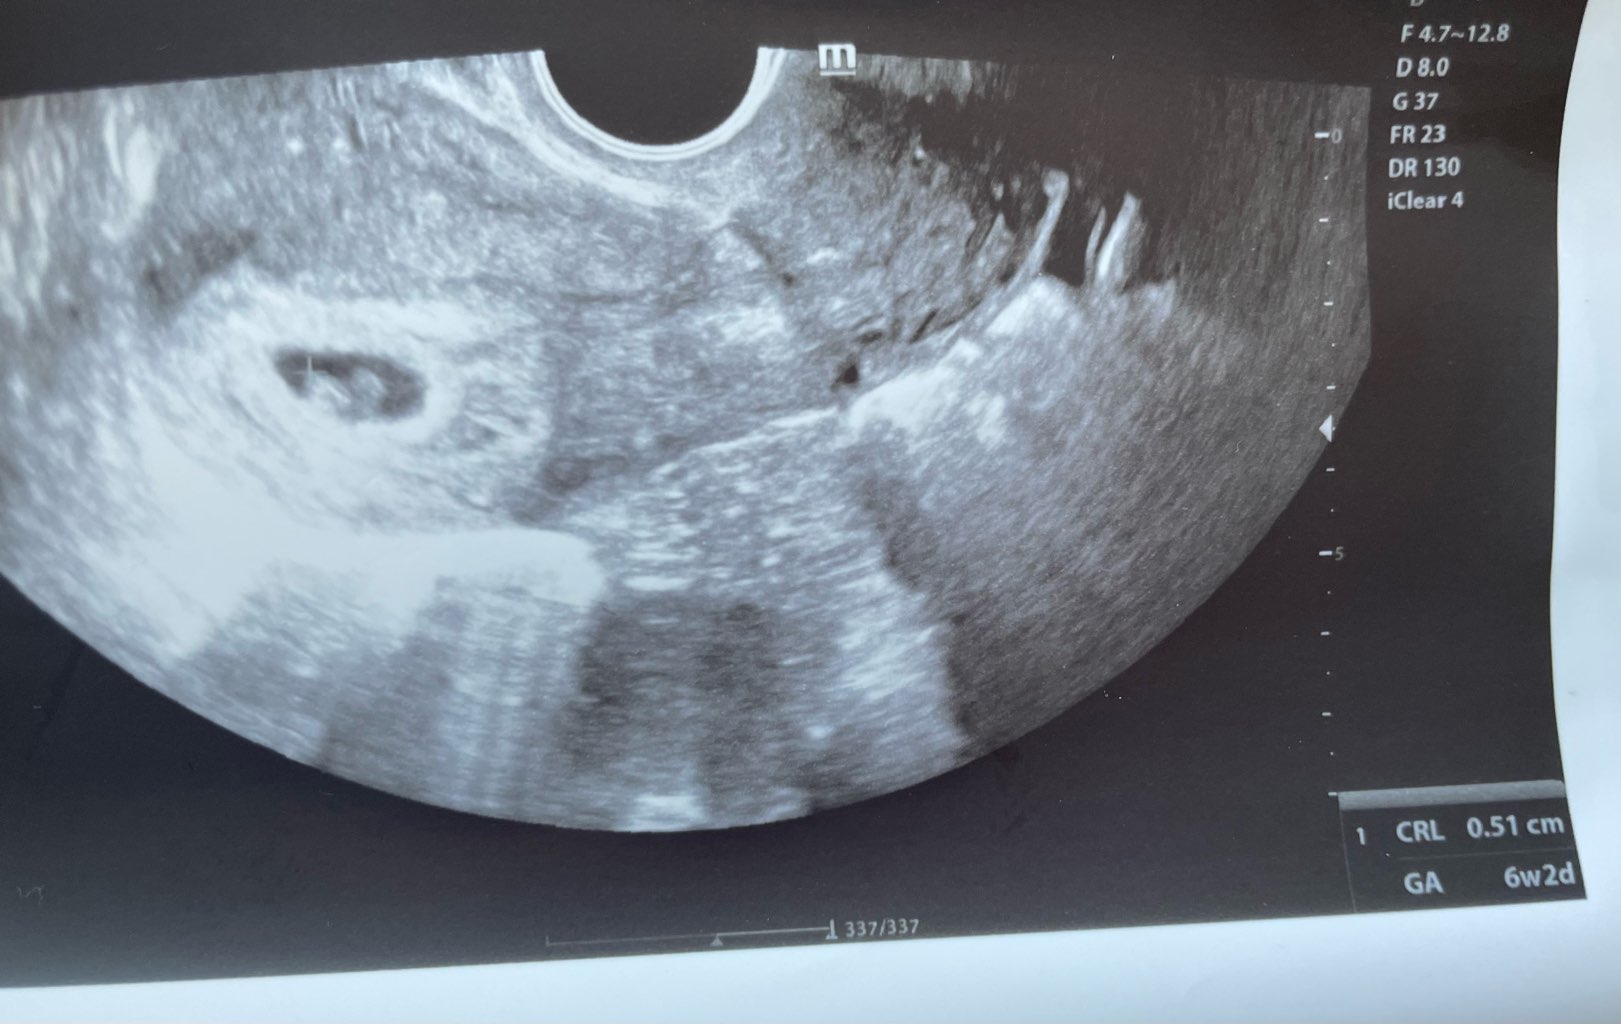

Na 11:10 mam wizytę, więc zaraz się zbieram do wyjścia.

Powodzenia! Trzymam kciuki!Na 11:10 mam wizytę, więc zaraz się zbieram do wyjścia.

Trzymamy kciukiNa 11:10 mam wizytę, więc zaraz się zbieram do wyjścia.

Godzina opóźnienia i same staruszki są przede mną